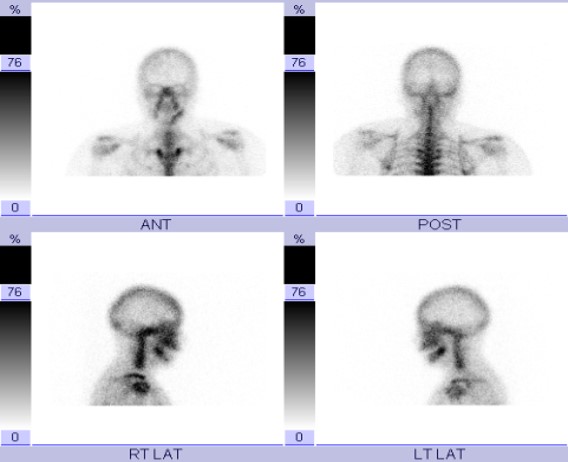

| Tc-99m MDP bone scan shows photopenic defects involving bilateral knee joints in the region of femoral and tibial condyles. |